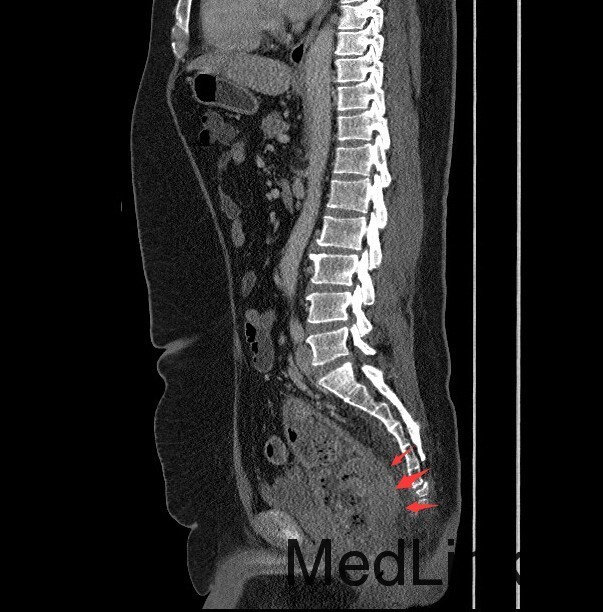

查体:肛查(KC位):肛周未见外痔,直肠指检可及环形多发内痔,部分质地较硬,有触痛,直肠壁可及多发结节,有触痛,指套退出有染血。 辅查:腹部CT示:直肠癌,累及肠壁全层,并周围肠系膜多发淋巴结转移,全身核素骨扫描结果提示:右侧坐骨轻度代谢活跃,建议定期复查以排除骨转移瘤可能,肿瘤标记物未见明显异常。肠镜示:1.直肠Ca?2.结肠息肉(已钳除)。

诊断:直肠癌? 治疗:入院后完善相关检查,肠镜活检病理示:B细胞源性非霍奇金淋巴瘤。肿瘤标记物未见明显异常。现患者要求暂缓手术治疗,办理出院。

讨论:胃肠道是原发性结外淋巴瘤最常见的累及部位。其中胃是最常见的发病部位,其次是小肠,而结肠和直肠少见。本例属于直肠淋巴瘤,属于少见肿瘤,影像表现与直肠癌相似,因此临床常常误诊为直肠癌,本例即误诊为直肠癌。影像学上只要认真观察一般能通过以下几点将两者鉴别开:淋巴瘤一般累及的肠段较长,肠壁较厚,肠腔变窄不明显,呈动脉瘤样扩张,没有肠梗阻表现,周围脂肪界面清晰。而大肠癌则相对较局限,常伴有肠腔的狭窄及肠梗阻的表现,而且常通过浆膜直接向周围浸润,周围脂肪间隙模糊。只要认真寻找这些影像征象,还是能够将两者较好的区别开来。